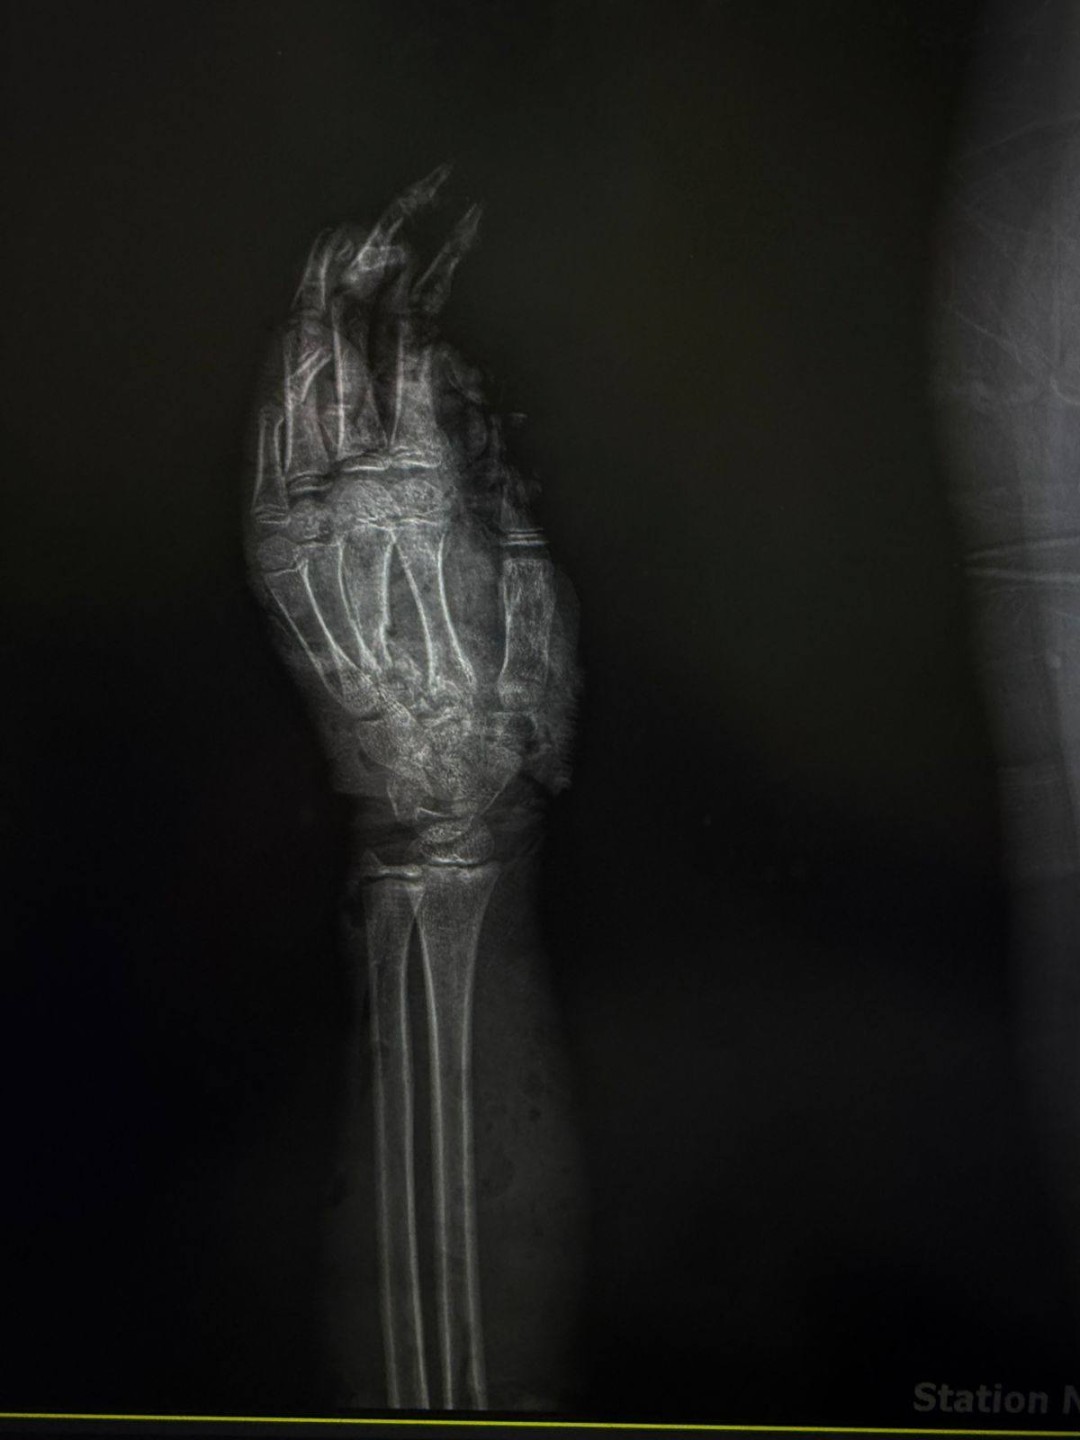

نجح فريق طبي متخصص بمستشفى الطوارئ الجديد بجامعة سوهاج، في إنقاذ ذراع طفل يبلغ من العمر 12 عامًا، عقب تعرضه لإصابة شديدة نتيجة حادث طاحونة قمح، أسفر عن تهتك كامل بأنسجة الذراع، وكسور متعددة بالأصابع، إلى جانب إصابة الأوتار والأعصاب.

وأشار الدكتور أحمد كمال، المدير التنفيذي للمستشفيات الجامعية ، إلى أن فريق وحدة جراحات اليد الميكروسكوبية قام بتثبيت الكسور الدقيقة بالأصابع، وتوصيل الأوتار والأعصاب المصابة، مع استكشاف الأوعية الدموية والتأكد من سلامتها، فيما تولى فريق جراحة التجميل إجراء رقعة جلدية لتعويض الجزء المتهتك المفقود من الذراع.